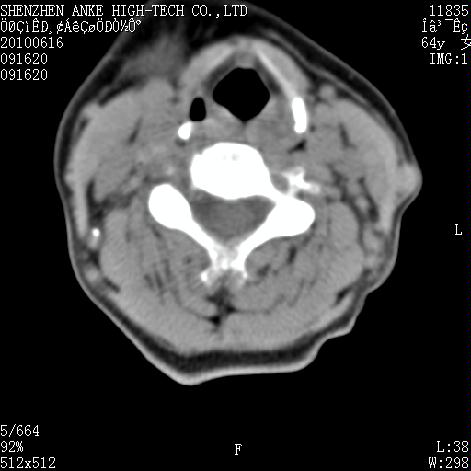

标题: CT27132:患者女,64岁,颈部及全身多处包块,现觉吞咽困难4 [打印本页]

标题: CT27132:患者女,64岁,颈部及全身多处包块,现觉吞咽困难4

右侧甲状腺占位,肿瘤可能性大,癌

右侧甲状腺癌伴右颌下腺淋巴结转移

右侧甲状腺癌伴淋巴结转移

右侧甲状腺癌伴淋巴结转移可能性大

右侧甲状腺癌伴淋巴结转移可能性大。

右侧甲状腺癌伴右颌下腺淋巴结转移!建议增强!